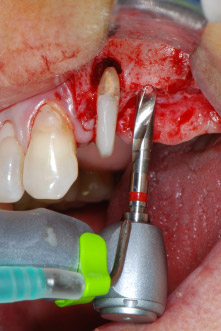

However, we maintained our initial plan to retain both teeth as temporary bridge abutments during the six-months osseointegration period of the implants. At reentry, the situation would have to be reassessed. First, in an attempt to manage the endo-perio problem, the remaining root surface was carefully debrided with piezoelectric equipment (Piezomed, W&H, used with the spatula-shaped insert S1, originally designed for erosion of the lateral sinus wall) (Fig. 4).

Then the apex was abraded with the same instrument to remove residual infected apical tissue and to reduce possible accessory root-canal ramifications (apicoectomy) (Fig. 5). A retrograde filling was not necessary because the orthograde filling had just been revised.

Fig. 4: To preserve the tooth as a temporary abutment, the periodontium was debrided with piezoelectric equipment …

buccal apex of tooth 24

Fig 5: ... and the buccal apex of tooth 24 was abraded with the same instrument (apicoectomy).